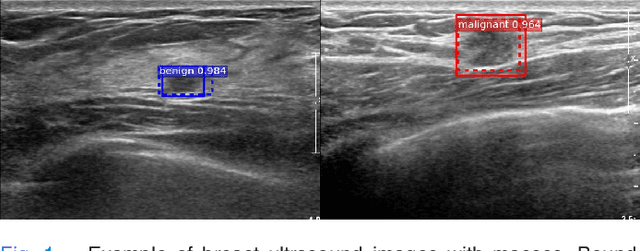

Abstract:We propose a framework for localization and classification of masses in breast ultrasound (BUS) images. In particular, we simultaneously use a weakly annotated dataset and a relatively small strongly annotated dataset to train a convolutional neural network detector. We have experimentally found that mass detectors trained with small, strongly annotated datasets are easily overfitted, whereas those trained with large, weakly annotated datasets present a non-trivial problem. To overcome these problems, we jointly use datasets with different characteristics in a hybrid manner. Consequently, a sophisticated weakly and semi-supervised training scenario is introduced with appropriate training loss selection. Experimental results show that the proposed method successfully localizes and classifies masses while requiring less effort in annotation work. The influences of each component in the proposed framework are also validated by conducting an ablative analysis. Although the proposed method is intended for masses in BUS images, it can also be applied as a general framework to train computer-aided detection and diagnosis systems for a wide variety of image modalities, target organs, and diseases.